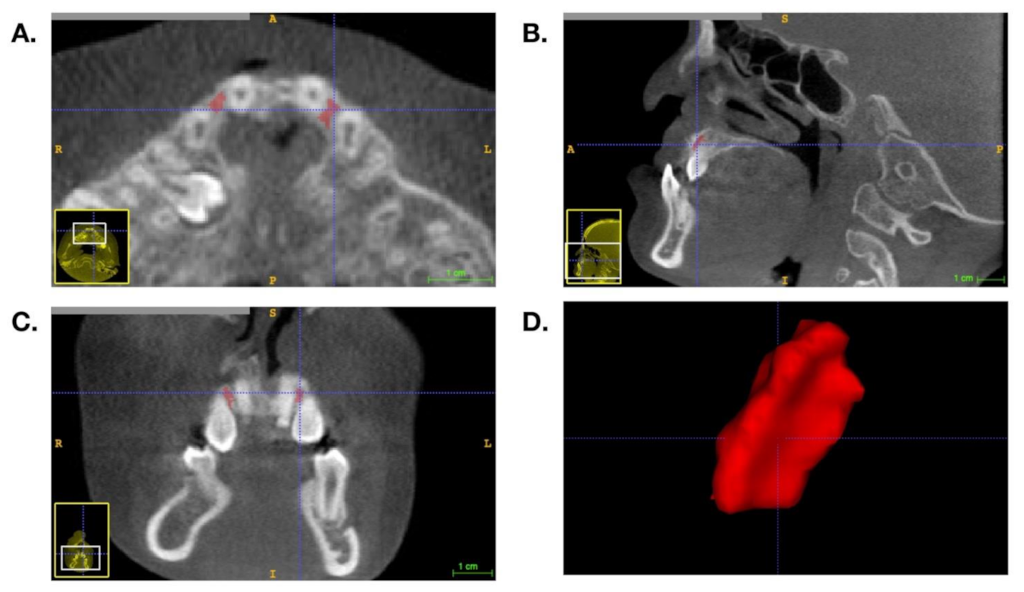

2.2. BMD Measurement and Volumetric Analysis